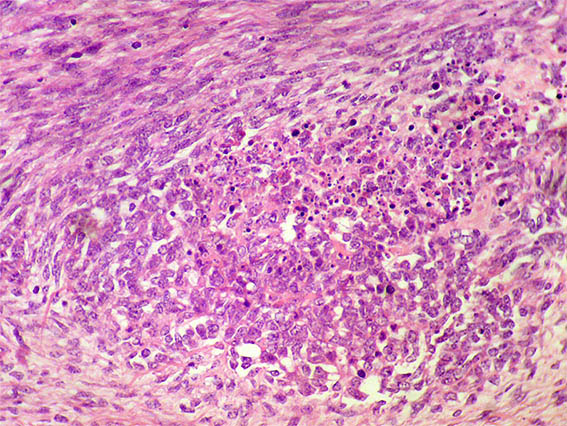

H&E, X100.

Figure 4. H&E, X200.